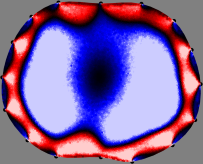

Figs. 3 and 4 compare the performance of the proposed FER method in (20) with the standard regularized least-squares method ((19) when is the identity matrix). The regularization parameter of the standard method was heuristically chosen for its best performance, and the parameter of the FER method was set to be one of three different values . The injection current was 1 mA at 100 kHz, and the frame rate was 9 frames per second. The reference frame at was obtained from the maximum expiration state. The measured data, , represent the voltage differences between each time and . The blue regions, which denote where conductivity decreased by inhaled air, increased during inspiration and decreased during expiration. The FER method with was clearly more robust than the standard method that produced more artifacts originated from the inversion process.

| Standard | |

||||||||||

| FER () | |